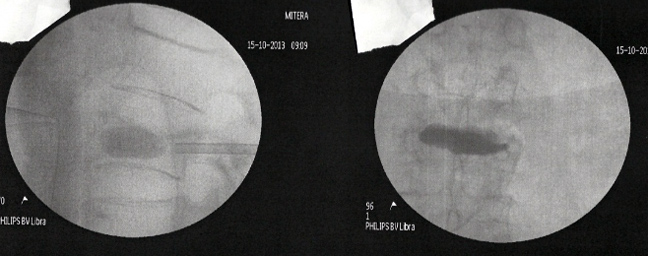

Η λύση αυτή ονομάζεται κυφοπλαστική. Χωρίς ανοικτή εγχείρηση, μέσω μίας χοντρής βελόνας (trocard) και παρακολουθώντας τη διαδρομή μέσω ακτινολογικής τηλεόρασης, εισάγεται μέσα στο σώμα του σπασμένου σπονδύλου ένα μπαλονάκι που φουσκώνει με νερό. Αναλόγως της πίεσης που ασκείται, ο σπόνδυλος διορθώνεται.

Στην κοιλότητα που δημιουργείται εισάγεται ακρυλικό τσιμέντο που όταν πήξει μετά μερικά λεπτά, καθιστά σταθερό και πάλι τον σπόνδυλο.

Η διαδικασία γίνεται με γενική νάρκωση και διαρκεί ¾ της ώρας. Μετά λίγες ώρες παραμονής στο νοσοκομείο, ο ασθενής επιστρέφει σπίτι του και από την επομένη κυκλοφορεί χωρίς πόνο, χωρίς κορσέ και χωρίς να γέρνει.